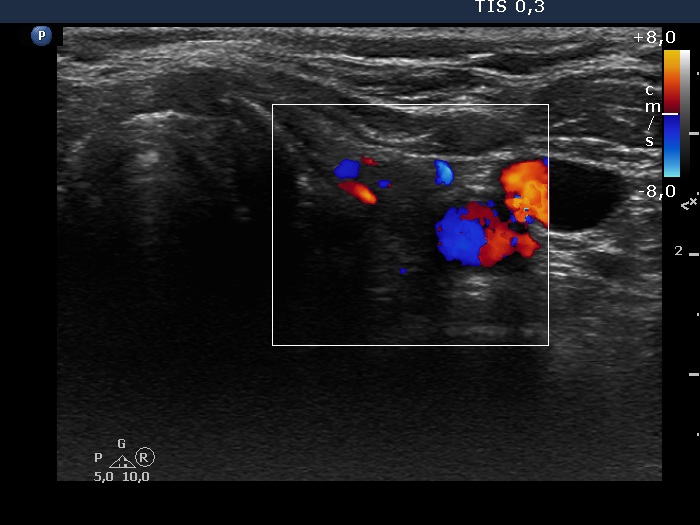

Left lobe, transverse view, color Doppler mode. The vascularization is not specific.